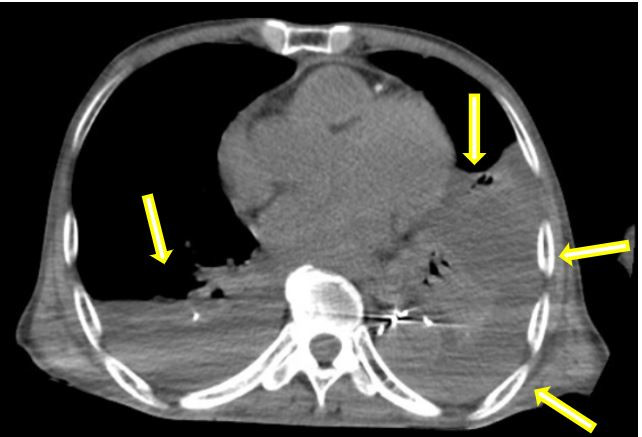

在患者轉(zhuǎn)運(yùn)過程中,血管外科急診團(tuán)隊(duì)、影像科、麻醉科、胸心外科、導(dǎo)管室、輸血科等相關(guān)科室已著手做好了急診相關(guān)預(yù)案。從患者的急診CTA上可以看到原有的胸主動(dòng)脈支架因血流動(dòng)力學(xué)影響,出現(xiàn)了近端Ⅰ型內(nèi)漏,大量血液經(jīng)由支架與主動(dòng)脈間的縫隙進(jìn)入假性動(dòng)脈瘤腔內(nèi),左側(cè)胸腔出現(xiàn)大量血腫,甚至出現(xiàn)了少量的心包積液。急診血常規(guī)顯示患者血紅蛋白才66g/L,顏老爺子已出現(xiàn)煩躁不安等譫妄表現(xiàn),為保障手術(shù)安全,團(tuán)隊(duì)立即聯(lián)系輸血科鄭春盛主任,有力地保障了患者術(shù)中用血。

巨大假性動(dòng)脈瘤壓迫左肺(箭頭示)

術(shù)后患者立即轉(zhuǎn)入重癥監(jiān)護(hù)病房(ICU),在李紅艷主任團(tuán)隊(duì)的精心管理下,患者一天后轉(zhuǎn)回血管外科病房,患者生命體征穩(wěn)定。根據(jù)術(shù)后CT復(fù)查結(jié)果,為解除肺部壓迫、緩解呼吸困難,術(shù)后胸心外科陳陽(yáng)天主任團(tuán)隊(duì)對(duì)患者進(jìn)行了胸腔穿刺引流,雙側(cè)胸腔引流出2000多毫升的不凝血性液體,這幾乎相當(dāng)于人體一半的血容量。經(jīng)過悉心的護(hù)理,患者術(shù)后恢復(fù)穩(wěn)定,呼吸、心率及全身狀況均得到了明顯改善,各項(xiàng)生化指標(biāo)平穩(wěn)恢復(fù),術(shù)后第十天,順利康復(fù)出院。

術(shù)前:雙側(cè)胸腔大量積血,雙肺受壓(箭頭示)

術(shù)后:經(jīng)引流后胸腔大量積液消失,肺部壓迫解除(箭頭示)